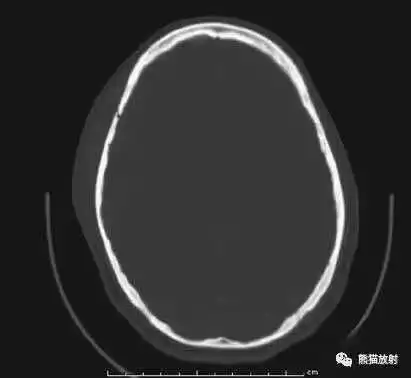

颅脑CT常用的三个窗(图A-C):

- 图A:骨窗(the bone window)

图A:骨窗;主要用于明确骨折、窦腔病变、颅内积气。